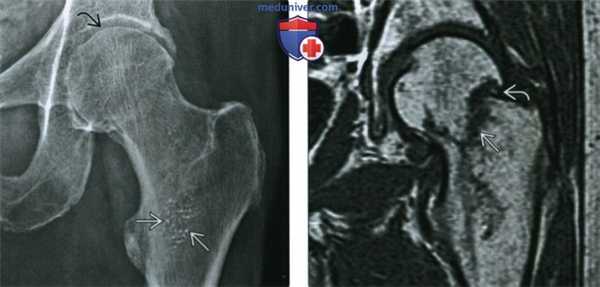

(Справа) КТ, костное окно, аксиальный срез: картина позвонка по типу «кость в кости». Обратите внимание на то, что форма визуализируемого склерозированного образования точно соответствует краям кортикального слоя. (Слева) Рентгенография в ПЗ проекции: пациент с остеопетрозом, осложненным подвертельным переломом. Обратите внимание на внутреннюю кость крыла подвздошной кости и характерное утолщение кортикального слоя бедренной кости.

(Справа) Рентгенография противоположной бедренной кости в ПЗ проекции после профилактической установки интрамедуллярного стержня: определяется выступ на латеральном кортикальном слое бедренной кости. Такой выступ, также наблюдаемый при бифосфонатной терапии, обусловлен весовыми нагрузками. Однако активность остеокластов недостаточная для его ремоделирования. Таким образом, это место является слабым, с высоким риском перелома.